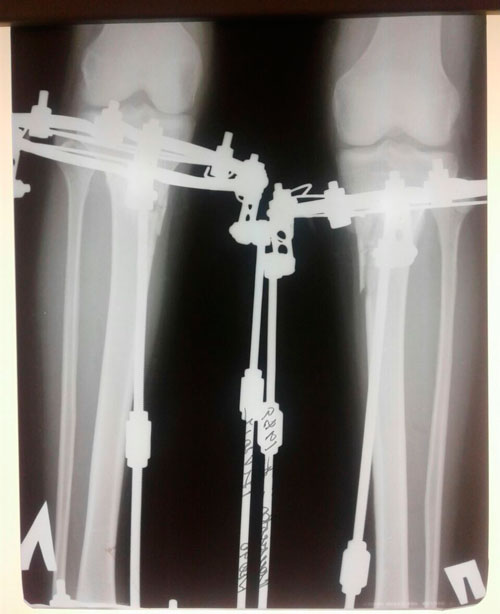

Дата операции 14.02.2018г.

Дата снятия аппаратов 12.06.2018г.

Срок лечения 120 дней.

Данная пациентка сняла аппараты (без разрешения Клиники) у себя в городе.

По условиям договора: Пациент обязан снимать аппараты в Клинике! В противном случае, Клиника не несёт ответственность за последствия и результат.

Прошу, относиться серьёзней к таким вещам.